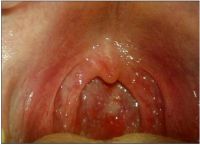

一般无明显全身症状。以咽部不适,发干、异物感或轻度疼痛、干咳、恶心,咽部充血呈暗红色,咽后壁可见淋巴滤泡等为主要临床表现。慢性咽炎患者,因咽分泌物增多,故常有清嗓动作,吐白色痰液。

- 检查:咽部慢性充血,加重。呈暗红色,或树枝状充血;咽后壁淋巴滤泡增生,或咽侧索肿大;咽粘膜增生肥厚,或干燥、萎缩、变薄,有分泌物附着.具各上述症状及1项或1项以上检查所见,即可诊断。